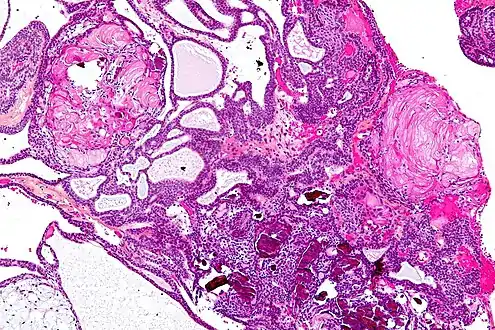

| Very low magnification micrograph of an adamantinomatous craniopharyngioma. HPS stain. | |

- Adamantinomatous craniopharyngiomas, which resemble ameloblastomas (the most common type of odontogenic tumor), are characterized by activating CTNNB1 mutations.

In the adamantinomatous type, calcifications are visible on neuroimaging and are helpful in diagnosis.

On macroscopic examination, craniopharyngiomas are cystic or partially cystic with solid areas. On light microscopy, the cysts are seen to be lined by stratified squamous epithelium. Keratin pearls may also be seen. The cysts are usually filled with a yellow, viscous fluid rich in cholesterol crystals. Of a long list of possible symptoms, the most common presentations include headaches, growth failure, and bitemporal hemianopsia.

Micrograph showing the characteristic features of an adamantinomatous craniopharyngioma - cystic spaces, calcifications, and "wet" keratin, HPS stain